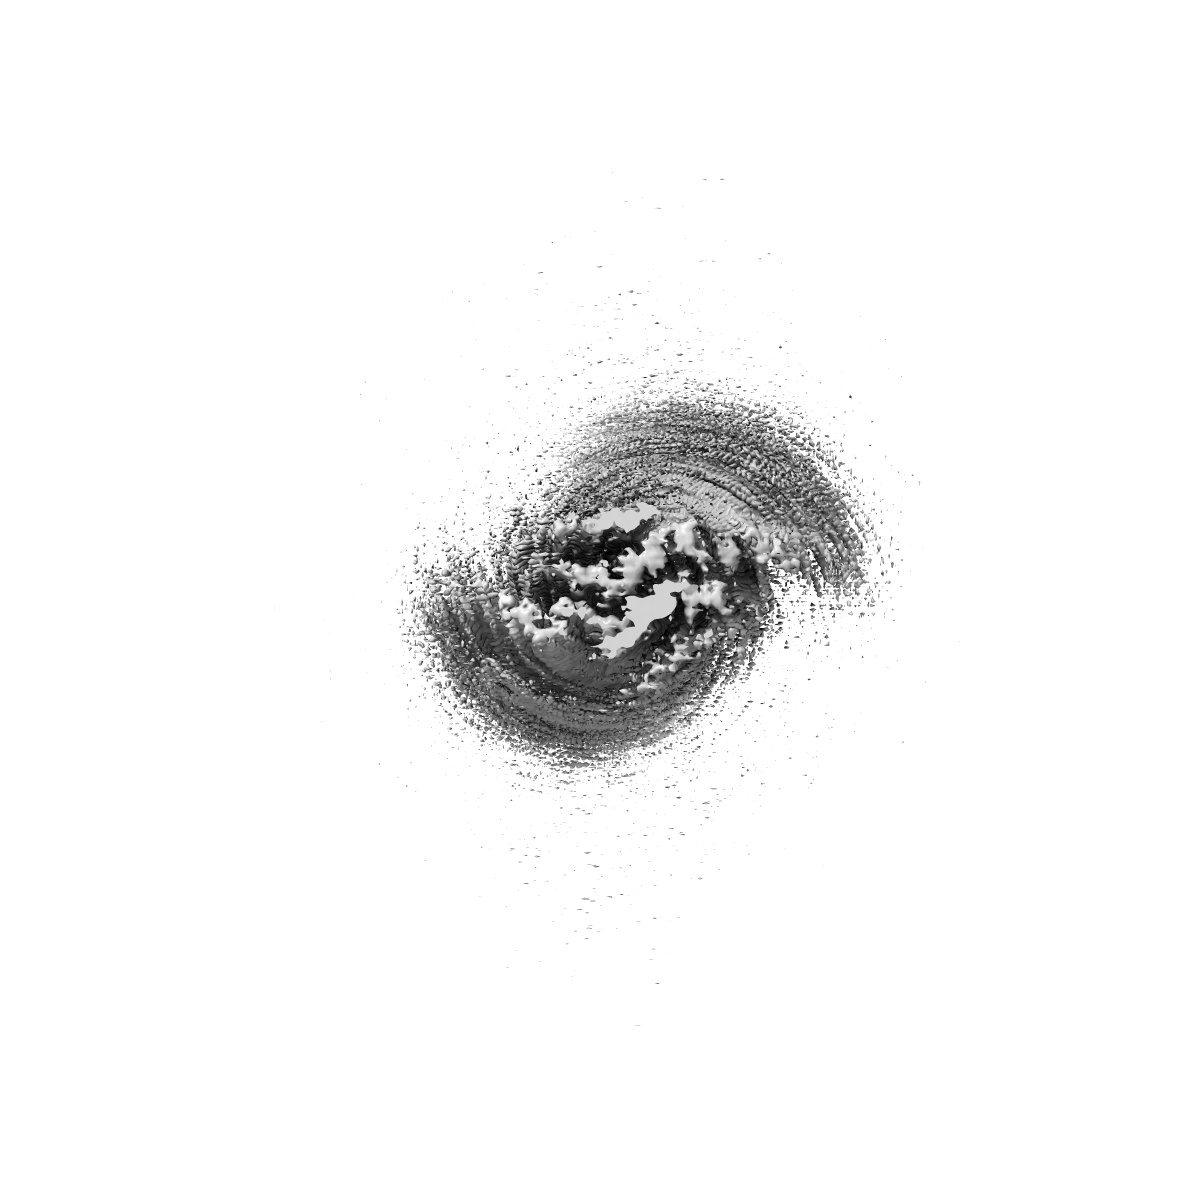

CryoEM Structure of 40-Residue Arctic (E22G) Beta-Amyloid Fibril Derived by Co-Analysis with Solid-State NMR | E22G Abeta40

Helical reconstruction2.5 Å

Sample: Amyloid Fibril of 40-Residue Beta-Amyloid with Arctic (E22G) mutation